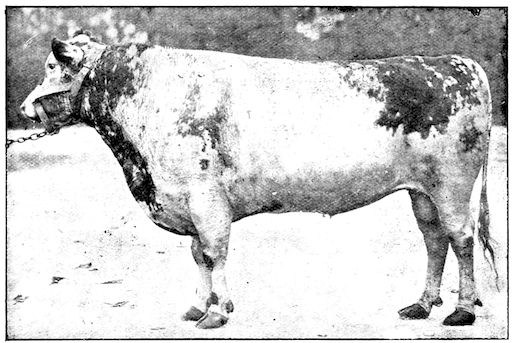

Fig. 6.—Osseous cachexia. This condition developed in two months, the last month of gestation and the first of lactation.

14Course. The development of the disease is slow, lasting from one to three months as a rule, and is little influenced by hygienic conditions. Good milking cows, however, seem to be most frequently attacked, probably because of the great losses of nutritive material which occur through the milk. The calves borne by such animals are often rachitic. Oxen are less commonly attacked. Horses rarely suffer from the disease in France, but frequently in Tonquin. Pigs reared on very poor soil seldom escape attack.

The disease has been observed in England, Scotland, United States, France, Belgium, and Jutland, and generally in districts with low-lying damp pastures. It attacks cows which are heavy milkers. Susceptibility appears to increase with advancing age.

Symptoms. The first symptoms are difficult to detect and interpret, especially at the commencement of an outbreak and in parts where the disease is rare they may lead to confusion and errors in diagnosis. On the other hand, in regions where the disease is common the practitioner will be able to form his diagnosis from the appearance of the first signs.

To render clear the mode in which the symptoms develop we may divide the progress of the disease into four phases, though this grouping is somewhat arbitrary.

91. The initial phase is not well marked, and is announced by digestive disturbance and by wasting. The former of these symptoms may be referred to some other cause, but consists in irregularity, diminution and sometimes perversion of the appetite. These earlier signs are soon followed by loss of spirits, and some interference with movement, but the symptoms only become of importance or attain their full development when the animals remain lying for a long period in the stable.

2. The second phase is characterised by more precise signs, which become almost pathognomonic. Difficulty in rising is added to the already existing tendency to remain lying, and to the interference with movement.

When lying down the patient no longer responds to the trifling stimulus, which a healthy animal needs to cause it to rise. It remains languid and apparently lazy, though in reality it experiences pain and difficulty on attempting to get up. The least muscular effort when lying down often causes it to moan, as do efforts to change its position or to walk. Even when standing still, it may appear to be in pain, and patients often assume a position similar to that of a horse suffering from laminitis.

At the end of this second phase, swellings appear, due to synovitis or arthritis of the extremities, synovitis of the sesamoid or navicular sheaths or to inter-phalangeal arthritis or arthritis of the fetlock joint. Weakness becomes marked, and the appetite is very irregular.

10Secretion of milk diminishes or ceases and abortion is not uncommon.

3. The third phase is characterised by fractures, and it is this peculiarity of the disease which has procured for it the names of fragilitas ossium, and osteoclastia. These fractures may affect any portion of the skeleton. Animals so suffering sometimes break a leg whilst trotting or the pelvis in simply jumping over a ditch; a collision with a fixed object like the jamb of the stable door, or a fall on the ground, may result in the fracture of one or several ribs.

Fig. 3.—Pig suffering from osseous cachexia (fourth stage).

Such shocks would be of no importance to a healthy animal, but to one suffering from osseous cachexia, any violence, or even the slightest muscular effort may be followed by fracture of the gravest character, involving even the vertebral column. In cows the pelvis, femur, and tibia are most frequently injured.

In horses, particularly in riding horses, fractures are commonest in the region of the forearm, cannon bone, and anterior phalanges. So extremely fragile are the bones at this stage that the horse represented herewith broke twelve ribs at one time by simply falling on its side. It is interesting to note that such fractures are never accompanied by any extensive bleeding. They have little tendency to repair, no real callus formation occurs, and on post-mortem examination one often finds the ends unconnected by temporary callus, worn, and rounded by reciprocal friction.

At this stage but under other circumstances, the animals show great reluctance to rise, remaining down for twelve to twenty-four hours without shifting their position. If forced to get up, they stand as though fixed in one position, the respiration and circulation become rapid, and they soon grow tired and fall.

114. The fourth phase, or period of osteomalacia, i.e. softening of the bones, is also the last. It is rarely seen in large animals like horses and oxen, because accidents so often accompany the preceding stages and necessitate slaughter; but it is common in goats and pigs.

In this phase the bones become elastic, soft and depressible, yielding to the pressure of the operator’s fingers.

Fig. 4.—Deformity of the face in the horse shown in Fig. 2.

The flat bones are particularly liable to this change, which is common to domesticated animals. The bones of the head are the first to suffer; later those of the pelvis. The lower jaw becomes swollen, particularly about the centre of the branches which may attain three, four, or five times, their normal thickness.

The depression in the submaxillary space disappears. The upper jaw undergoes similar changes, becoming deformed and thickened until the cavities of the sinuses and the hollow appearance of the palate are lost, while the face is so changed that it cannot be recognised as that of a horse, goat, etc.

The molar teeth are almost buried, their tables alone being visible at the bottom of a depression, the edges of which rise above the neighbouring parts (pig).

Mastication is clearly impossible, the jaws appear paralysed, the muscles powerless, and only swallowing is possible, a fact which explains why life is only prolonged to this stage in animals which can be fed with a spoon or bottle (pigs and goats). The bones of the cranium, although greatly changed in texture, are always less deformed than those of the face.

The changes are such that it is often easy with a mere post-mortem knife to cut the head completely in two. Osseous tissue, properly so-called, has disappeared.

All the constituent tissues, with the exception of the skin and muscles, i.e., the bone, periosteum and aponeuroses, have the appearance and consistence on section of the fibro-lardaceous tissue seen in chronic inflammation.